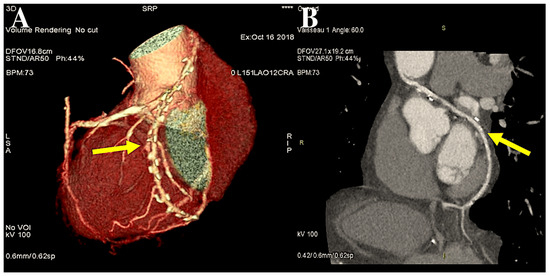

However, in cases of target vessels situated in the proximal obtuse marginal position, the graft utilised for CABG is anastomosed anteriorly or alternatively on the opposite side of the aorta through the transverse sinus (Figure 2A,B).

The figure illustrates the post-processing of CT angiography of CABG using volume rendering (A) and two-dimensional curved imaging with automatic tracking. (B): CT angiographic control of the radial artery at 27 years. The radial artery (yellow arrow) was utilised as the second target conduit on the second obtuse branch of the left coronary circumflex artery and the posterior descending artery. Abbreviations: CABG, coronary artery bypass grafting; CT, computed tomography.